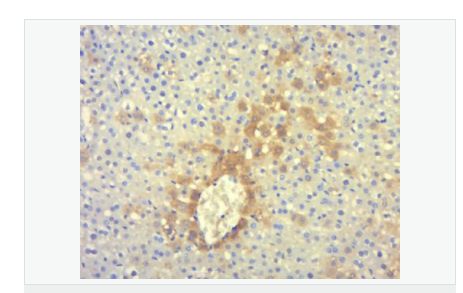

交叉反應:Human,Mouse,Rat(predicted:Dog,Pig,Cow,Rabbit,GuineaPig) 推薦應用:IHC-P,IHC-F,IF,Flow-Cyt,ELISA

| 產品應用 | ELISA=1:5000-10000 IHC-P=1:100-500 IHC-F=1:100-500 Flow-Cyt=1ug/Test IF=1:100-500 (石蠟切片需做抗原修復) not yet tested in other applications. optimal dilutions/concentrations should be determined by the end user. |